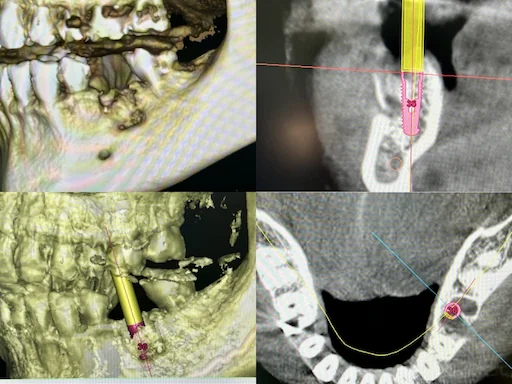

Patientenfall: Implantatplanung für Zahn 36

Bereits bei der 3D-Planung des Implantats ist zu erkennen, dass durch die verschiedenen Resektionsansätze große Knochendefizite entstanden sind.

Patientenfall Implantologie: Unterkiefer Zahn 36 - Bohrschablone

In diesem Fall wurde das Implantat etwa sechs Wochen nach der Zahnentfernung eingesetzt, das Knochenersatzmaterial eingebracht sowie mit Eigenblutmembranen und Memlock-Membranen zur besseren Wundheilung abgedeckt und daraufhin die Wunde plastisch verschlossen.